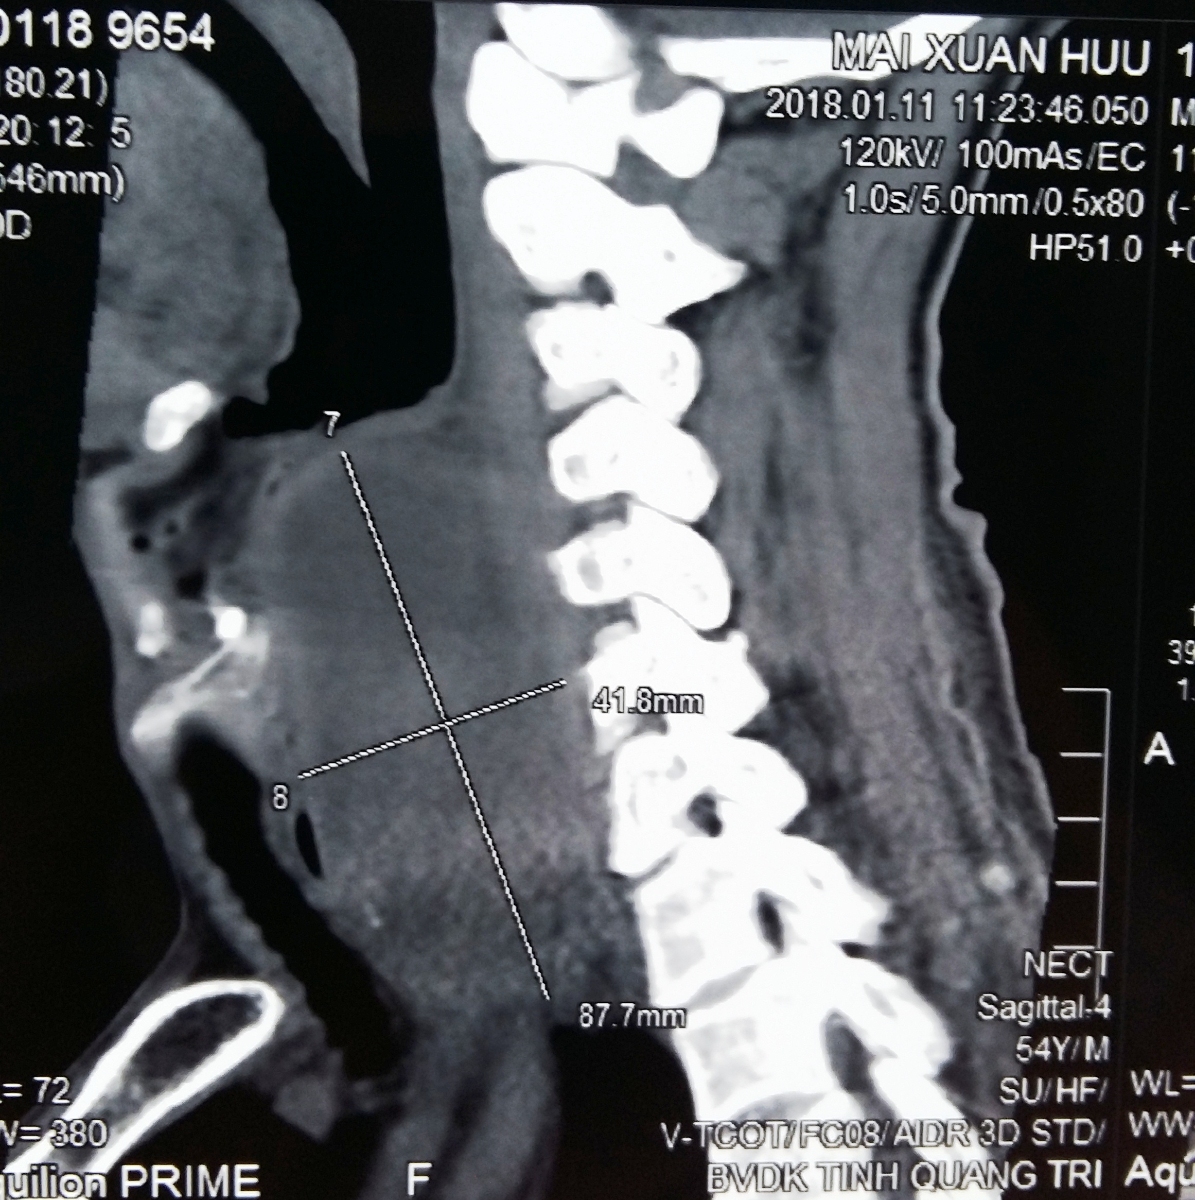

Kết quả khám lâm sàng, nội soi, siêu âm, chụp CT 160 lát cắt được Bệnh viện Đa khoa tỉnh Quảng Trị thực hiện cho thấy dị vật là mẩu xương cá dài 1,5cm nằm sát ngực và khối áp xe có kích thước rất lớn ngoài thực quản sau tuyến giáp trước cột từ sau miệng thực quản lan xuống trung thất trên có nguy cơ vỡ và đe dọa tính mạng củaông Mai Xuân Hữu. Tiên lượng bệnh nặng,Bệnh viện Đa khoa tỉnh Quảng Trị đã có phương án chuyển tuyến trênnhưng ông Hữu và người nhà của ông nhất quyết ở lại. Ngay sau đó, cuộc hội chẩn của các bác sỹ chuyên khoa Tai-mũi-họng, khoa Ung buớu và khoa Chẩn đoán hình ảnh đã thống nhất phẫu thuật cạnh cổ, dẫn lưu áp-xe và lấy dị vật.

Mẩu xương cá chèn ép thực quản, đe dọa tính mạng của ông Mai Xuân Hữu

Ngày 13/1/2018, kíp bác sỹ khoa Ung bướu và khoa Tai-mũi-họng đã tiến hành phẫu thuật mởkhoang cạnh cổ bên trái, vén cơ ức đòn chũm, tách cơ giáp móng, đẩy động mạch cảnh chung ra ngoài, cắt động mạch giáp giữa, vén tuyến giáp, bộc lộ thực quản để hút 50 ml dịch mủ và lấy ramẩu xương cá sắc nhọn dài hơn 1,5 cm và dẫn lưu áp xe. Sau 10 ngày điều trị, sức khỏe củaông Hữu đã ổn định và làm thủ tục ra viện vào ngày 30/1/2018.